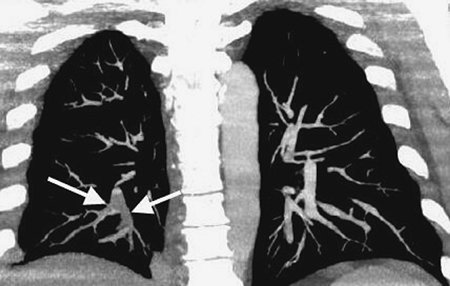

FIGURE 17-2. Acute PE. Coronal CTPA of a 43-year-old man with acute shortness of breath shows extensive intraluminal filling defect within the right lower lobe pulmonary arteries (arrows).